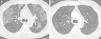

A 73-year-old man, former smoker with a history of alcoholic cirrhosis and unresectable HCC, consulted due to a 1-month history of progressive dyspnea on exertion. Two months before the consultation, he had undergone hepatic radioembolization with I-90 resin microspheres, with an expected lung dose of 10Gy. Before treatment, lung scintigraphy after injection of technetium-99m-labeled albumin macroaggregates (MAA-99mTc) in the hepatic artery had revealed a lung shunt fraction of 10%. On physical examination, the patient presented tachypnea, bilateral crackles on pulmonary auscultation, and peripheral oxygen saturation of 88%, with no signs of heart failure. Chest computed tomography revealed a “crazy paving” pattern, with elevation of the right hemidiaphragm (Fig. 1A). The need for a diagnostic bronchoscopy was discussed, but refused by the patient. Given his history of radioembolization and hepatopulmonary shunt, a presumptive diagnosis of pneumonitis due to radioembolization was established. Treatment began with 20 mg/day prednisone for 2 months, and the patient's clinical condition improved with resolution of changes on tomography (Fig. 1B).

Clinical symptoms include cough, dyspnea and fever. Tomography findings appear 1–2 months after therapy in the form of ground glass infiltrates and septal thickening. The treatment of choice is systemic corticosteroids.2 Our patient presented clinical and radiological findings consistent with radiation pneumonitis. It is important that this complication is recognized, and it must be taken into account among patients undergoing hepatic radioembolization.